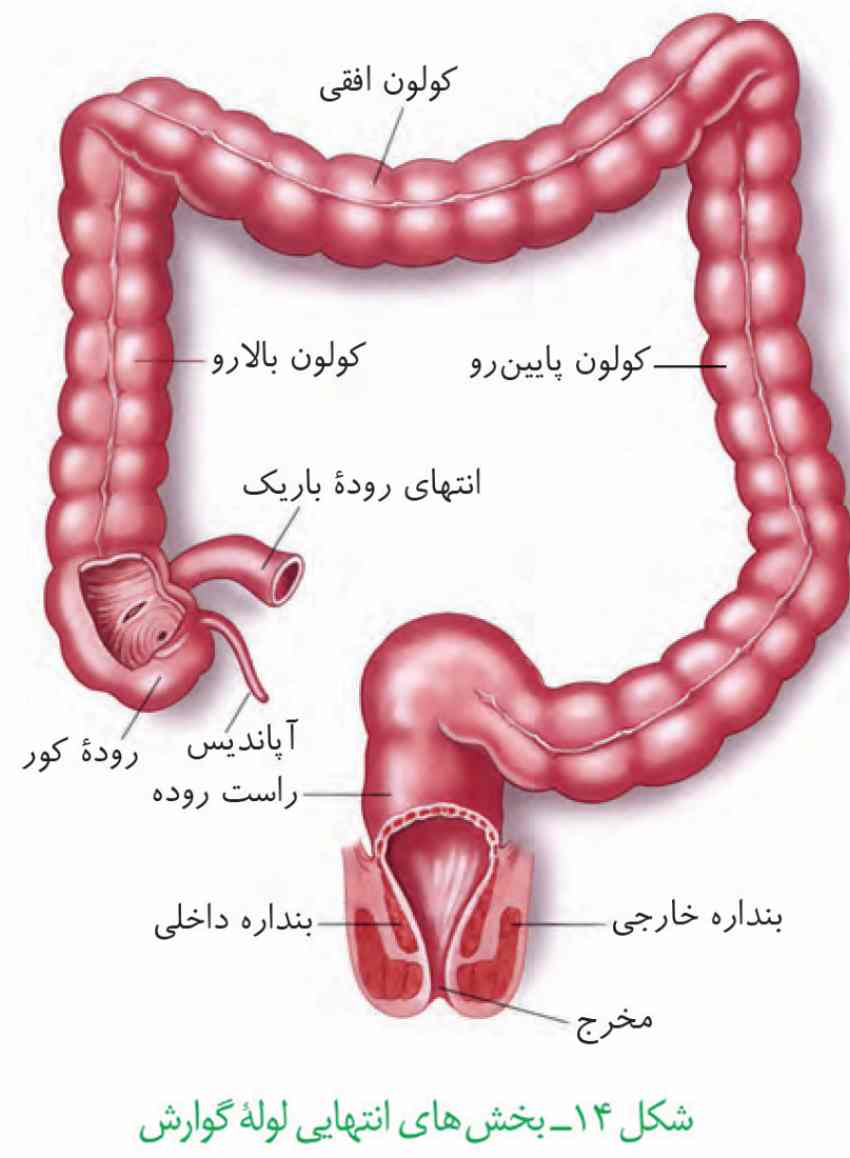

در سطح جلویی کلیه راست بخشی از کبد و کولون بالارو و در سطح جلویی کلیه چپ بخشی از لوزالمعده و کولون پایینرو قرار دارد.

۳-نیمه راست کولون افقی پایینتر از نیمه چپ آن باشد.